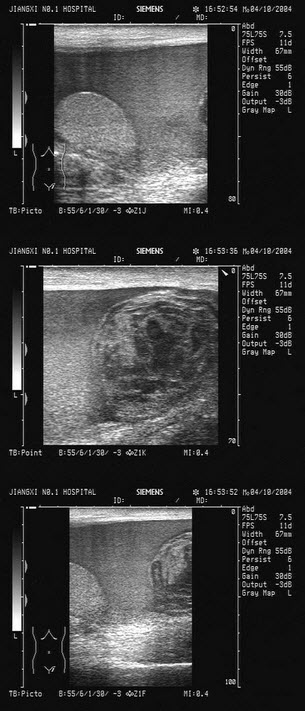

12、单项选择题

某患者因血尿就诊,前列腺超声声像图如下,生化检查PSA增高,最可能的诊断为()

A.前列腺脓肿

B.前列腺炎

C.前列腺良性增生

D.前列腺癌

E.前列腺囊肿

13、单项选择题

患者女76岁,上腹部胀痛不适半年余,加重1周。剑突下B超检查如图所示,根据超声声像图诊断为()

A.胃癌

B.胃溃疡

C.肾癌

D.结肠癌E、胃炎

E.胆总管蛔虫